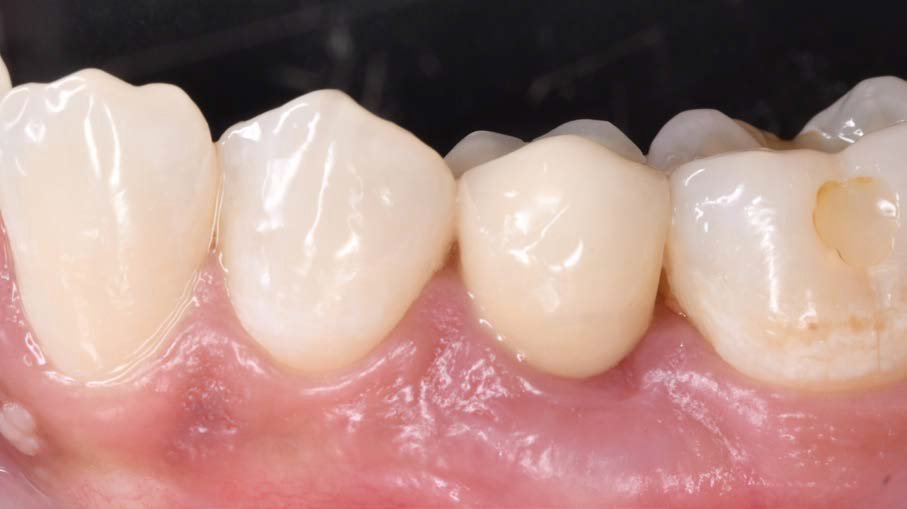

Figure 9: Clinical image after prosthetic restoration |

After six months, the soft tissue remained stable, and the papillae were well-formed. The case met all expectations for “pink-white aesthetics.” I was very satisfied with both the surgical and prosthetic results.